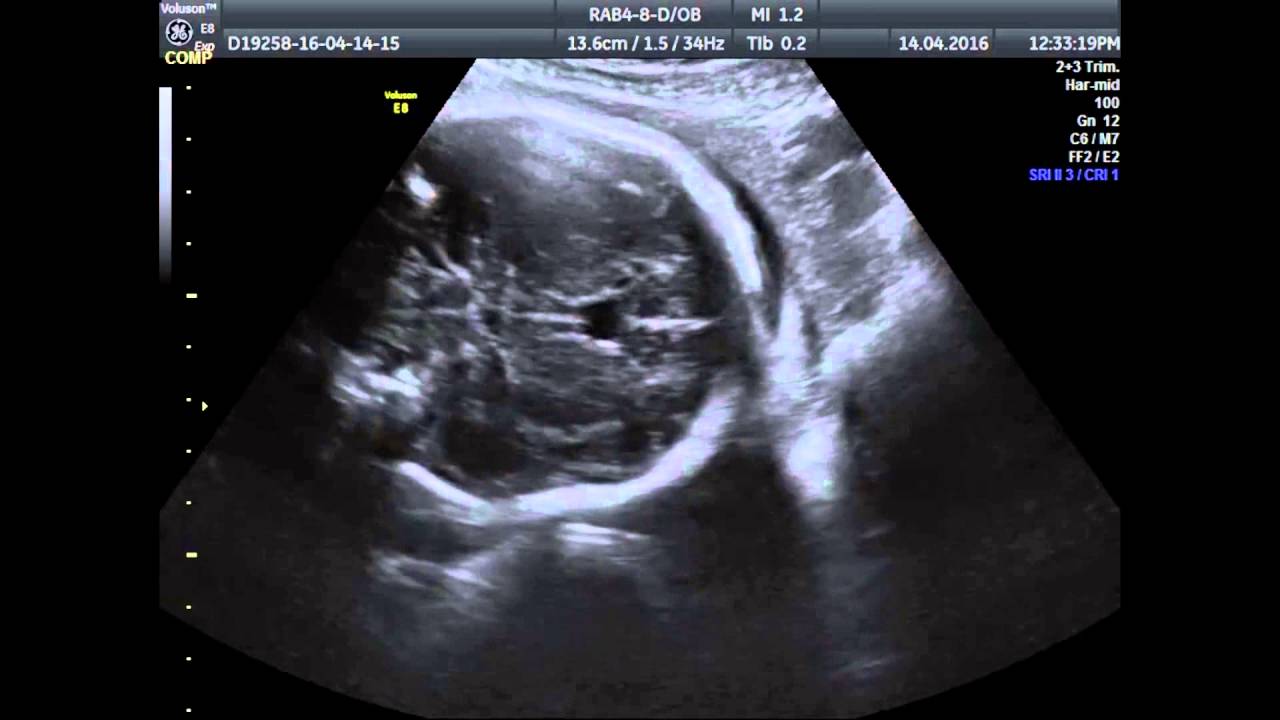

Новообразование характеризуется скоплением цереброспинальной жидкости в пространстве между двумя пластинами (слоями) прозрачной перегородки, которая разделяет передние отделы мозга и мозолистое тело. Чаще формируется в период внутриутробного развития. Признаки отклонения от нормы заметны в перинатальный период, обнаруживаются в ходе УЗИ-исследования плода.

Стенка формируется в первом триместре беременности. Ультразвуковая диагностика контролирует щелевые параметры между листами пропорционально сроку неделям беременности.